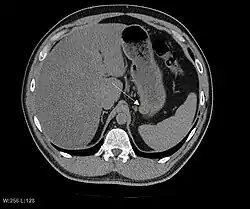

The purpose of radiologic imaging is to locate the lesion, evaluate for signs of invasion and detect metastasis. Features of GIST vary depending on tumor size and organ of origin. The diameter can range from a few millimeters to more than 30 cm. Larger tumors usually cause symptoms in contrast to those found incidentally which tend to be smaller and have better prognosis.[4][20] Large tumors tend to exhibit malignant behavior but small GISTs may also demonstrate clinically aggressive behavior.[21]

Barium fluoroscopic examinations and CT are commonly used to evaluate the patient with abdominal complaints. Barium swallow images show abnormalities in 80% of GIST cases.[21] However, some GISTs may be located entirely outside the lumen of the bowel and will not be appreciated with a barium swallow. Even in cases when the barium swallow is abnormal, an MRI or CT scan must follow since it is impossible to evaluate abdominal cavities and other abdominal organs with a barium swallow alone. In a CT scan, abnormalities may be seen in 87% of patients and it should be made with both oral and intravenous contrast.[21] Among imaging studies, MRI has the best tissue contrast, which aids in the identification of masses within the GI tract (intramural masses). Intravenous contrast material is needed to evaluate lesion vascularity.

Preferred imaging modalities in the evaluation of GISTs are CT and MRI,[23]: 20–21 and, in selected situations, endoscopic ultrasound. CT advantages include its ability to demonstrate evidence of nearby organ invasion, ascites, and metastases. The ability of an MRI to produce images in multiple planes is helpful in determining the bowel as the organ of origin (which is difficult when the tumor is very large), facilitating diagnosis.

Since GISTs arise from the bowel layer called muscularis propria (which is deeper to the mucosa and submucosa from a luminal perspective), small GIST imaging usually suggest a submucosal process or a mass within the bowel wall. In barium swallow studies, these GISTs most commonly present with smooth borders forming right or obtuse angles with the nearby bowel wall, as seen with any other intramural mass. The mucosal surface is usually intact except for areas of ulceration, which are generally present in 50% of GISTs. Ulcerations fill with barium causing a bull's eye or target lesion appearance. In contrast-enhanced CT, small GISTs are seen as smooth, sharply defined intramural masses with homogeneous attenuation.

Large GISTs

As the tumor grows it may project outside the bowel (exophytic growth) and/or inside the bowel (intraluminal growth), but they most commonly grow exophytically such that the bulk of the tumor projects into the abdominal cavity. If the tumor outstrips its blood supply, it can necrose internally, creating a central fluid-filled cavity with bleeding and cavitations that can eventually ulcerate and communicate into the lumen of the bowel. In that case, barium swallow may show an air, air-fluid levels or oral contrast media accumulation within these areas.[21][25] Mucosal ulcerations may also be present. In contrast-enhanced CT images, large GISTs appear as heterogeneous masses due to areas of living tumor cells surrounding bleeding, necrosis or cysts, which is radiographically seen as a peripheral enhancement pattern with a low attenuation center.[20] In MRI studies, the degree of necrosis and bleeding affects the signal intensity pattern. Areas of bleeding within the tumor will vary its signal intensity depending on how long ago the bleeding occurred. The solid portions of the tumor are typically low signal intensity on T1-weighted images, are high signal intensity on T2-weighted images and enhanced after administration of gadolinium. Signal-intensity voids are present if there is gas within areas of necrotic tumor.[22][26][27]

Features of malignancy

Malignancy is characterized by local invasion and metastases, usually to the liver, omentum and peritoneum. However, cases of metastases to bone, pleura, lungs and retroperitoneum have been seen. In distinction to gastric adenocarcinoma or gastric/small bowel lymphoma, malignant lymphadenopathy (swollen lymph nodes) is uncommon (<10%) and thus imaging usually shows absence of lymph node enlargement.[20] If metastases are not present, other radiologic features suggesting malignancy include: size (>5 cm), heterogeneous enhancement after contrast administration, and ulcerations.[4][20][28] Also, overtly malignant behavior (in distinction to malignant potential of lesser degree) is less commonly seen in gastric tumors, with a ratio of behaviorally benign to overtly malignant of 3-5:1.[4] Even if radiographic malignant features are present, these findings may also represent other tumors and definitive diagnosis must be made immunochemically.